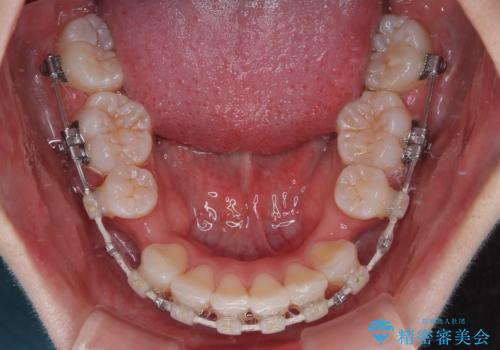

- 矯正装置

- 審美装置

下顎はデコボコが気になっていたため、上下左右第一小臼歯4本を抜去して、ワイヤー装置にて口元の突出感を改善するよう矯正治療を行うこととしました。

- 口を閉じたときに飛び出してしまう上顎前歯を気にして来院された患者様です。